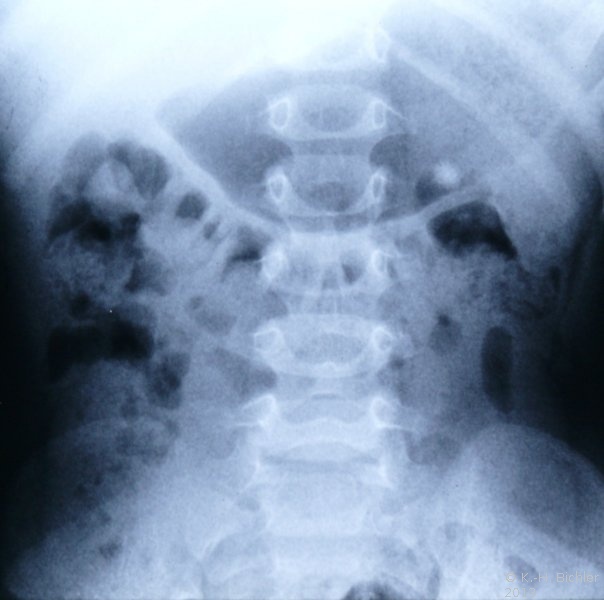

Mittlerweile liegen ausreichende klinische Erfahrungen mit der Anwendung der Extrakorporalen Harnsteinzertrümmerung auch im Kindesalter vor. Kleine Nierenbecken- bzw. partielle Nierenbeckenausgusssteine können daher endoskopisch bzw. mit ESWL entfernt werden.

Begünstigt wird das Verfahren bei Kindern, da die durch die Stoßwelle entstehenden Steinfragmente in Folge größerer Elastizität des Ureterlumens die ableitenden Harnwege leichter als beim Erwachsenen passieren. Auf die früher benötigten speziellen Vorrichtungen zur Lagerung von Kindern auf dem Stoßwellengerät kann bei modernen Geräten verzichtet werden. Die Kinder werden entsprechend der Erwachsenenpositionierung gelagert. Die ESWL wird im Kindesalter immer in Allgemeinnarkose durchgeführt (Abbildungen 3,4)